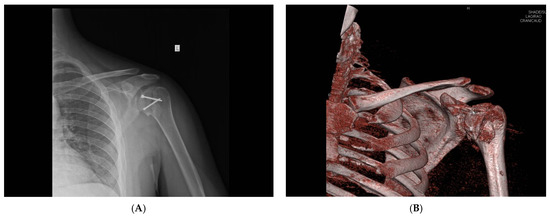

The average value of Constant’s point scale for the operated shoulder was 84.14 (ranging from 50 to 93) (Table 1), indicating a good result. Postoperatively, a follow-up X-ray and CT scan were performed, which demonstrated the appropriate positioning of the allograft in all twenty patients (Figure 5).

Figure 5. Postoperative X-ray (A) and three-dimensional CT view (B) of the operated shoulder (photo from the personal archive of intraoperative photos of the author).